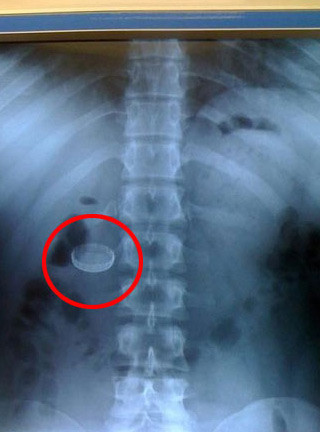

Bugünün fotoğraf galerisinde haberlerle birlikte, eğlenceli anların görüntülerini, siyaset sahnesinden kareleri, Türkiye ve dünya ülkelerinden gelen ilginç anların resimlerini bulabilirsiniz. Foto galeride ünlülerin ve sporcuların görüntüleri de yer almaktadır.